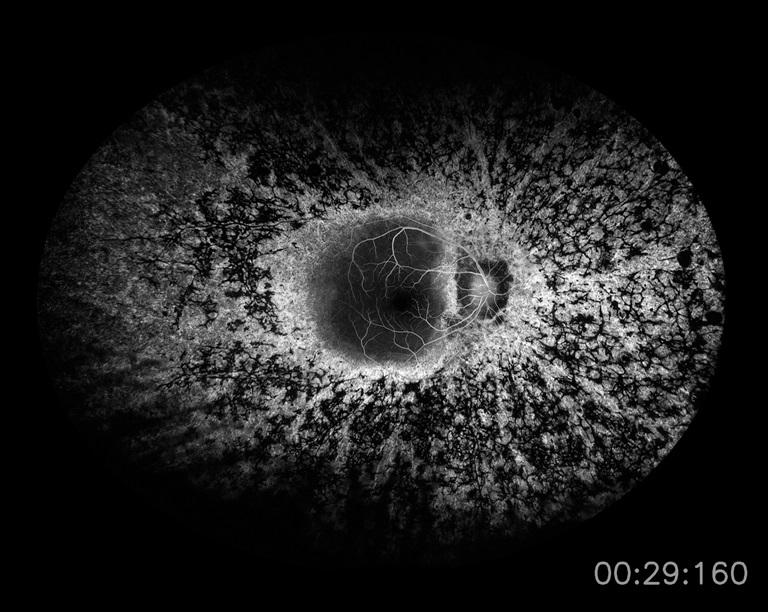

Unknown Unilateral Dx, Not Thought to be Retinitis Pigmentosa

Presented by Sara Ash, BAThis photograph received Honorable Mention in the category "Retinal Fluorescein Angiography" and was displayed at the 2024 ASCRS/OPS Society Exhibit.